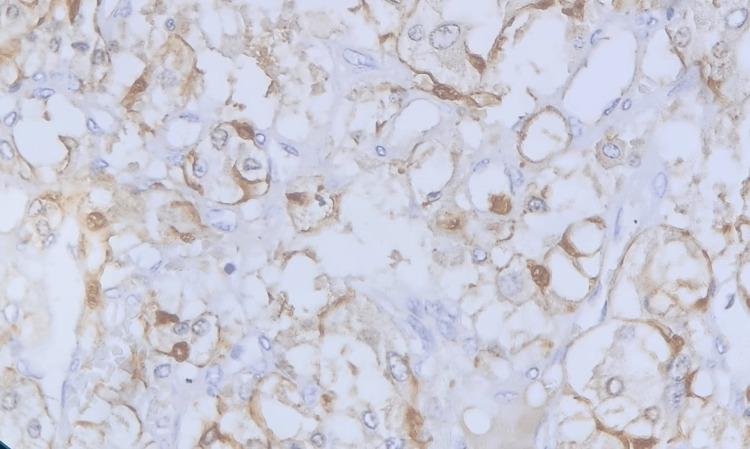

A pheochromocytoma is an uncommon tumor that originates from the chromaffin cells of the adrenal medulla. Also, adrenal tissue not located in its typical position is referred to as ectopic adrenal tissue. It is relatively uncommon in adults and is usually asymptomatic. Therefore, a pheochromocytoma arising from ectopic adrenal tissue is even a rarer finding and presents as a unique diagnostic challenge. A 20-year-old man presented with vague abdominal pain, and upon imaging, a mass located behind the liver was initially discovered. Subsequently, it was identified as a mass growing in an ectopic adrenal gland. He underwent exploratory laparotomy and resection of the mass. A pheochromocytoma in an ectopic adrenal gland was confirmed by histopathology.

摘要

嗜铬细胞瘤是一种起源于肾上腺髓质嗜铬细胞的罕见肿瘤。此外,位于非典型位置的肾上腺组织被称为异位肾上腺组织。它在成年人中相对少见,通常无症状。因此,起源于异位肾上腺组织的嗜铬细胞瘤更是罕见,是一个独特的诊断挑战。一名20岁男性因腹部隐痛就诊,影像学检查最初发现肝脏后方有一个肿块。随后,该肿块被确定为在异位肾上腺中生长。他接受了剖腹探查并切除了肿块。组织病理学证实为异位肾上腺中的嗜铬细胞瘤。